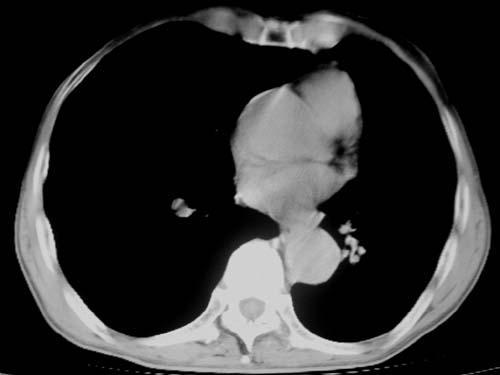

标题: CT19736:男,76岁,咳嗽,胸痛 [打印本页]

标题: CT19736:男,76岁,咳嗽,胸痛

支持左上肺周围型肺癌性并空洞形成伴胸椎转移。

左上沟癌空洞形成并胸椎转移。

考虑癌性空洞并胸椎转移。

空洞内壁有多发结节,支持癌性空洞。